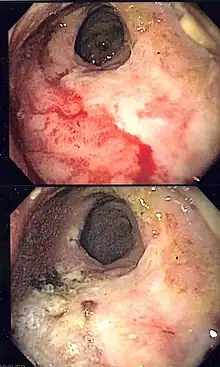

| Endoscopic image of radiation associated vascular ectasias (RAVE) before and after therapy with argon plasma coagulation. | |

Endoscopy is the mainstay of diagnosis for radiation damage to the rectum, with either colonoscopy or flexible sigmoidoscopy. RAVE is usually recognized by the macroscopic appearances on endoscopy characterized by vascular ectasias.[8] Mucosal biopsy may aid in ruling out alternate causes of proctitis, but is not routinely necessary and may increase the risk of fistulae development.[6] Telangiectasias are characteristic and prone to bleeding.[3] Additional endoscopic findings may include pallor (pale appearance), edema, and friability of the mucosa.